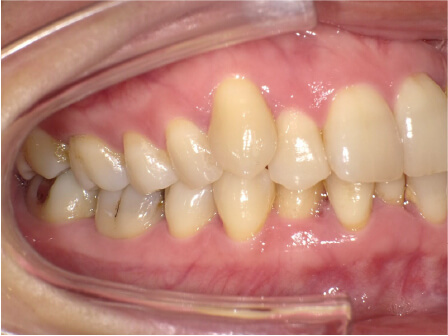

叢生の症例

41歳

/

女性

相談内容

横から見た時のガタガタが気になる

カウンセリング・診断結果

インビザライン、正中は上11に合わせていく、抜歯・拡大装置・IPR・アタッチメントOK

治療内容・方法

アライナー矯正

術後の経過・現在の様子

クリアライナー使用

治療のリスク

痛み・歯根吸収・歯肉退縮・虫歯・後戻り

費用・治療期間

880,000円、7ヶ月

トレーニングなど